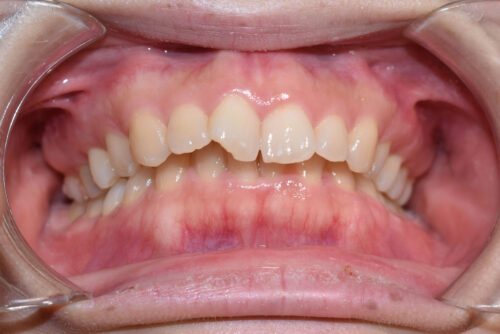

ワイヤー矯正治療10か月後です。

ワイヤー期間 10か月, 13回来院

かみ合わせをあげながら

歯の並びをそろえていくことで

歯をぬかなくても

出っ歯にならずに

非抜歯矯正治療で

咬合させることができます。